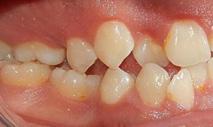

Estudios de inicio intraorales en la fotografía de frente, tenemos la línea media dental superior se encuentra desviada a 1 mm a la izquierda y la línea media dental inferior se encuentra desviada 2 mm a la derecha (Figura 2). En la oclusal superior la forma de arco cuadrada (Figura 3). En la lateral derecha una relación molar clase II y relación canina clase II (Figura 4), izquierda una relación

Dentista y Paciente 42 Caso clínico

Figura 1. Extraoral frente sonrisa y perfil de inicio. Figura 2. Intraoral de frente.

Figura 3. Oclusal superior. Figura 4. Derecha, izquierda. Figura 5. Izquierda inicio. Figura 6. Radiografía lateral de cráneo y radiografía panorámica.